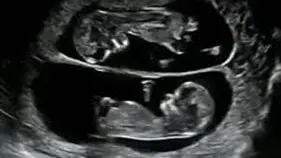

¿Qué se realiza en el ultrasonido de estos embarazos?

• ❤ Evaluación de la corionicidad, es decir si se trata de un embarazo gemelar con una placenta en la que ambos gemelos la comparten o bien dos placentas, una para cada gemelo, ya que de acuerdo a ello será la vigilancia en estos embarazos

• ❤ Si son embarazos gemelares con una sola placenta, la evaluación y el seguimiento deberá ser más estrecho, ya que que hay mayor riesgo de complicaciones en estos embarazos.

• ❤ La ecografía es el mejor método diagnóstico no sólo para identificar una gestación gemelar, sino también para catalogarla y especificar su corionicidad (número de placentas) y su amniocidad (número de bolsas).